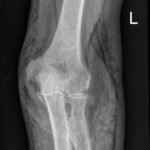

X-Rays of the elbow revealed diffuse striated lucencies throughout the soft tissue, consistent with extensive subcutaneous air throughout the superficial and deep tissues. There was no evidence of a fracture.

The patient discussed here had a LRINEC score of 0. However, the physical exam finding of crepitus, coupled with his history of immunocompromised status and subcutaneous air on X-ray made the diagnosis of NSTI seem likely. However, upon surgical exploration there was no evidence of a NSTI. The most likely mechanism for the subcutaneous air found on this X-ray was that the wound at the elbow acted as a one-way valve for air to enter and collect within the soft tissues. This case is an example of how clinical suspicion and diagnostic scores may not align. Regardless, it is important to keep in mind the clinical picture when deciding to contact consultants. It is recommended, as demonstrated in this case, to obtain a surgical consultation when clinical suspicion is high for a life-threatening diagnosis despite a low risk based on a decision score. It is best to keep in mind that a low LRINEC score does not exclude the diagnosis and that if there is a high suspicion for a NSTI a surgeon should be consulted prior to calculation of a LRINEC score.